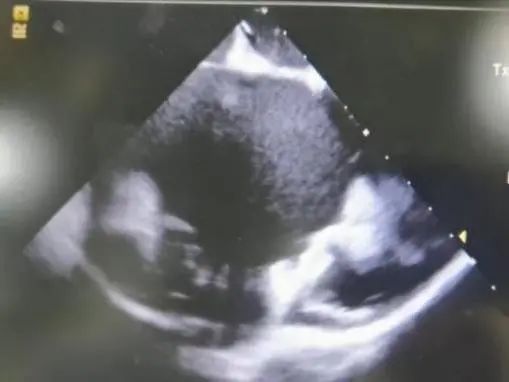

在ICE指导和DSA影像下,沿猪尾将鞘管推送至目标位置,撤猪尾后,选择33mm封堵器植入,整个封堵器展开的过程,退鞘动作慢而稳,封堵器一次展开后即在预期封堵位置区间,DSA下通过肝位(RAO30 CAU20)和足位(RAO1 CAU20)造影确认其位置,结合ICE下显示,封堵器植入到了非常完美的位置。完全符合成功的标准,即PASS 原则:P:位置准确;A:固定良好;S:大小合适,压缩比15%;S:封堵完全,无残余分流;完美释放,手术顺利结束(图5,6)。

图6. ICE下评估PASS原则,封堵器释放